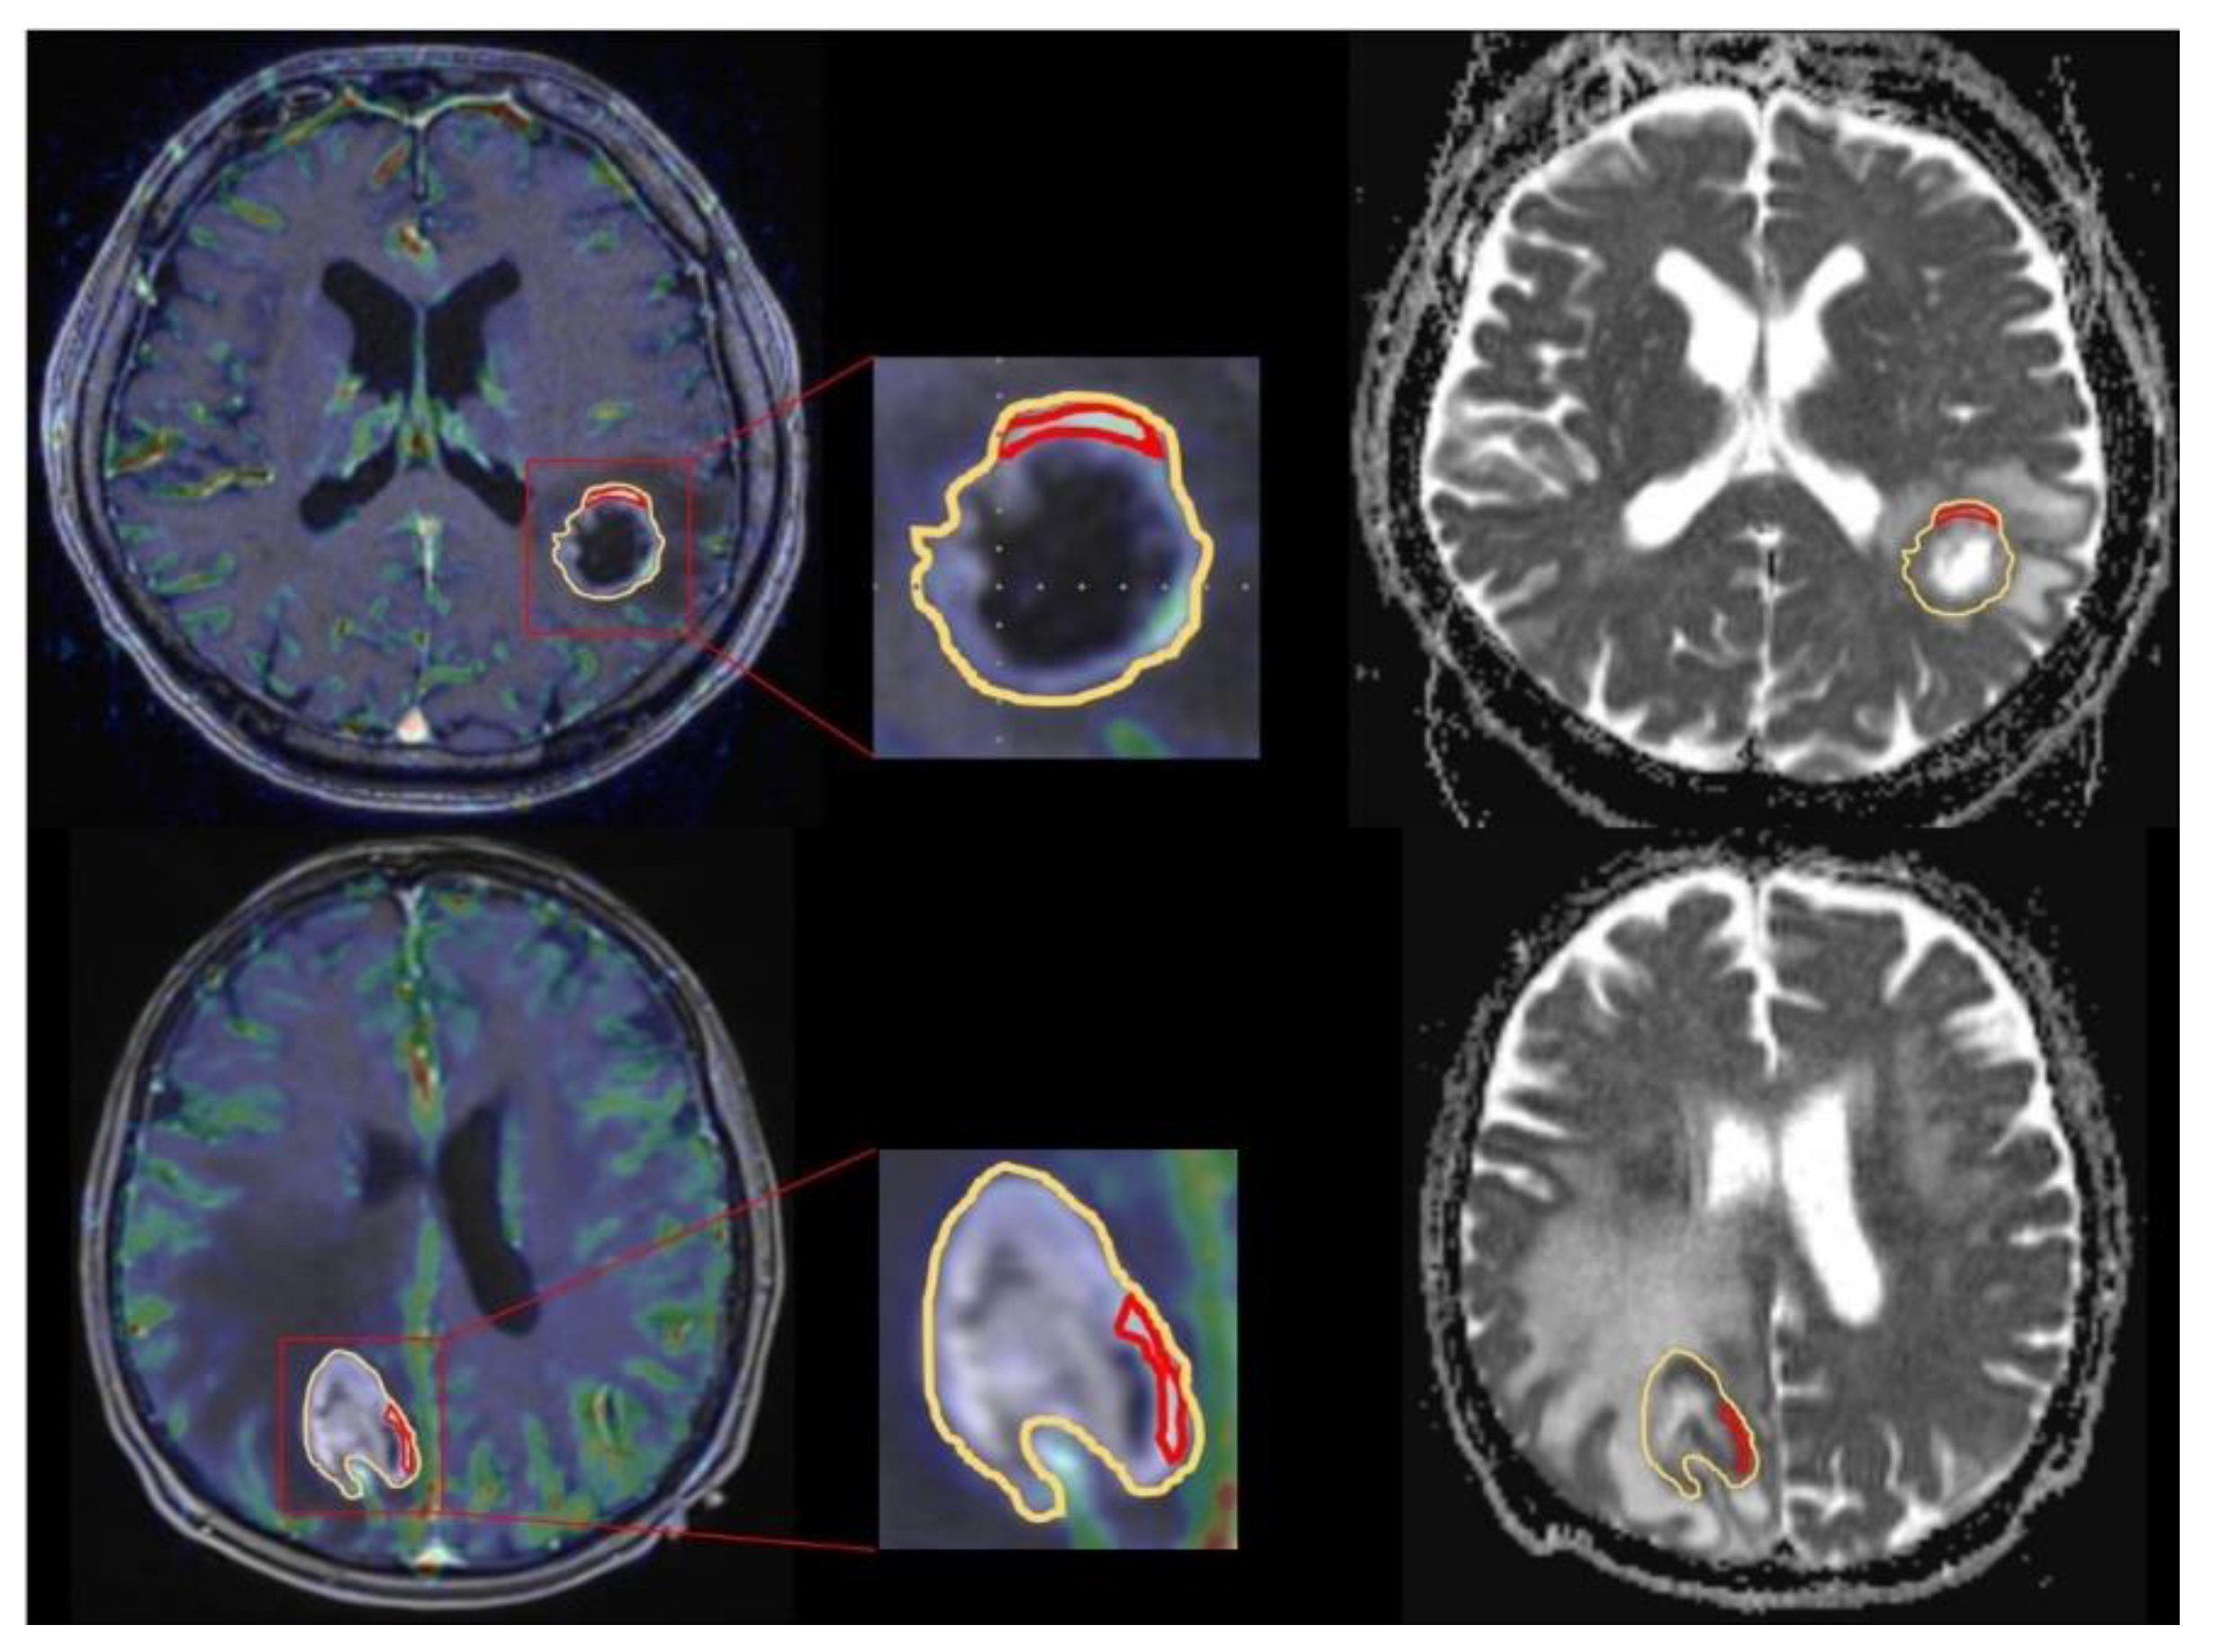

Afterwards ROIs were copied to the exact same region in the corresponding ADC map. Figure 1 shows exemplary ROI measurements in a GBM patient as well as a PCNSL patient.

Figure 1. Exemplary apparent diffusion coefficient (ADC) and cerebral blood volume (CBV) measurement in a glioblastoma (GBM) and primary central nervous system lymphoma (PCNSL) patient. Exemplary ADC measurement of a selective region of interest (ROI)(red) in the contrast enhanced tumor area with the highest CBV and a unselective ROI (yellow) comprising the whole contrast enhancing lesion for a GBM patient (upper line) in comparison to a PCNSL patient (bottom line). After placing the ROIs carefully in the fused CBV × contrast enhanced T1 sequence map (right) ROIs are copied to the exact same position in the corresponding ADC maps (left).